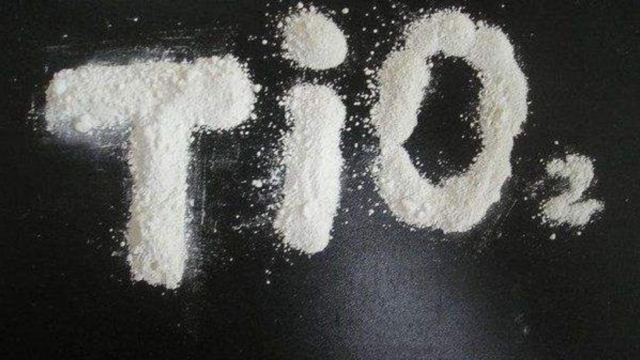

Dentifrice, chewing-gums et bonbons : l’insidieux danger du dioxyde de titane